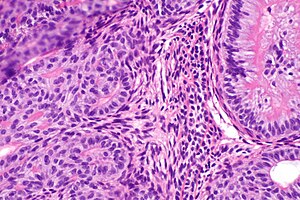

Файл:Skin papilloma (low zoom).jpg

Папиллома кожи

Тканевый атипизм проявляется в нарушении пространственных и количественных соотношений между компонентами ткани. Клеточный атипизм характеризуется изменениями морфологии клеток: увеличением ядер, изменением соотношения ядра и цитоплазмы, появлением аномальных митозов. Органоидность строения означает, что опухоль частично сохраняет структурные особенности той ткани, из которой она происходит.

Для злокачественных опухолей характерны как клеточный атипизм (изменение базальной мембраны, нарушение соотношения объёмов цитоплазмы и ядра, увеличение числа митозов), так и тканевой атипизм (нарушение соотношений между стромой и паренхимой, сосудами и стромой).